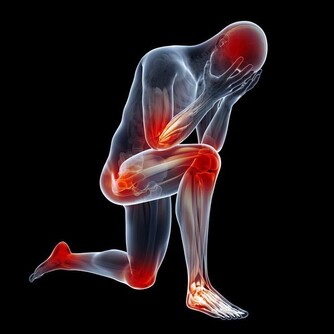

1、睡眠

如果在沒有感冒的情況下,睡覺前反复咳嗽,並且存在胸悶、胸痛的情況,就要考慮是否肺部出現問題,有可能是肺炎所致。

2、呼吸

一般來說,如果人的肺部功能下降,那麼呼吸就會不規律,如變得急促或變得衰弱等,有時需要深呼吸才可以獲取足夠的氧氣。

所以,想知道自己的肺好不好,可以通過自身的呼吸情況判斷,具體將手指放在鼻孔下方,觀察呼吸是否均勻、正常即可。若是有呼吸困難、急促的現像出現,有可能是肺部出現病變,需要多加重視。